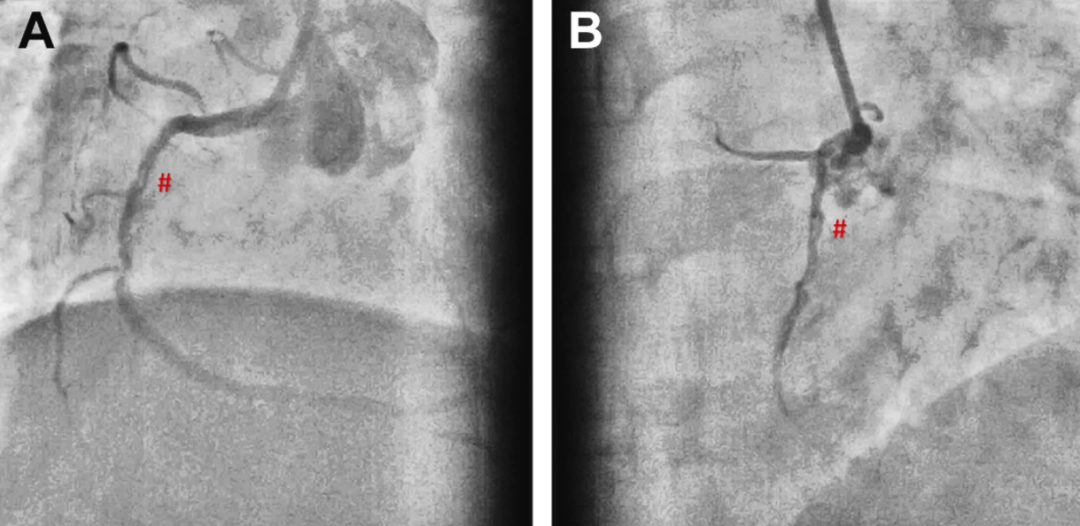

一位48岁男性STEMI患者,其LAD的造影结果不明确(血栓性闭塞或1型SCAD)(图6A至6F),且TIMI血流2级;同时,RCA中段和钝缘支分支疑似3型SCAD。

图6 病例3:患者血管造影和左前降支(LAD) OCT 图像

(A)左前斜头位视图显示右冠状动脉(RCA)中段疑似3型 SCAD(∗)。(B)右前斜位视图显示右冠状动脉(RCA)疑似 SCAD(∗)(C-E)。左前降支(LAD)中段可见可疑充盈缺损(1型 SCAD/再通血栓)伴有造影剂延迟清除(红色箭头),以及左回旋支(LCX)/钝缘支(OM)疑似3型 SCAD(黄色箭头)(F)。左前降支(LAD)最终 PCI 结果(G 和 H)。左前降支(LAD)管腔被向内推挤;假腔用 # 标示(I)。OCT的 L 模式:真腔被假腔(#)向内推挤。

鉴于诊断不确定性,对LAD进行OCT检查(图6G 至6I),显示了真腔被壁内血肿向内推移,从而确诊了SCAD。随即使用1:1切割球囊和药物洗脱支架进行了PCI,实现了TIMI血流3级。

一位50岁女性,无合并症,表现为活动后呼吸困难、LVEF降低,造影提示三支血管病变,LAD疑似SCAD(图7A)。

图7 病例4:患者血管造影和左前降支(LAD) OCT 图像

(A)血管造影显示左前降支(LAD),提示管腔细薄呈管状,边缘锐利,高度怀疑为左前降支(LAD)的2A/3型 SCAD。(B)OCT 显示纤维钙化斑块,最小管腔面积为0.89mm2,无提示 SCAD 的特征。

她此前已在两个不同的医疗中心就诊,因症状持续来到本院。造影复查强烈提示LAD存在SCAD、RCA远端和钝缘支闭塞。然而,OCT(图7B)检查发现在造影上不可见的LAD纤维钙化病变,并未显示任何SCAD特征。随后,采用切割球囊对病变进行预处理,成功为患者实施了血管成形术。